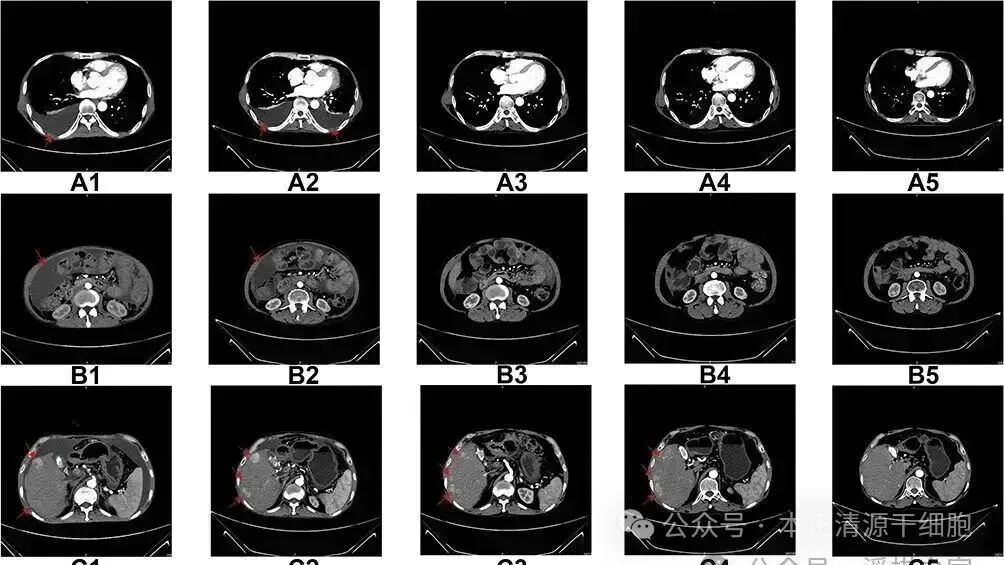

一项发表在国际期刊《Oncotargets and Therapy》上的研究报道了一个晚期肝细胞癌患者接受NK细胞疗法后的积极成果,展示了NK细胞疗法的有效性和安全性。这名男性患者在2016年6月被确诊患有晚期弥漫性肝细胞癌,根据TNM分期标准被定为T3N1M1,即属于第IV期。

自2017年3月至2018年7月期间,该患者接受了共计17轮的NK细胞治疗,每轮治疗间隔一个月,每次连续输注两天。值得注意的是,在此期间患者并未接受其他形式的治疗。

研究结果显示,在经历了17个月的治疗后,患者外周血中NK细胞的比例增加了接近七倍,免疫功能也显示出改善或至少没有恶化。此外,患者的肝功能指标保持在正常范围内,除了甲胎蛋白(AFP)以外的其他肿瘤标志物水平也有所下降,生活质量有了显著提升。

图片

在进行了六个疗程后,患者胸部和腹部积液显著减少。至治疗结束时,患者的状态得以保持,并且右肝叶中的多处肿瘤病灶体积有所缩小。

尤其重要的是,截至报道时,患者的生存时间已经超过48个月,即超过四年的时间。这一案例为NK细胞疗法在晚期肝细胞癌治疗中的应用提供了有力的证据支持。